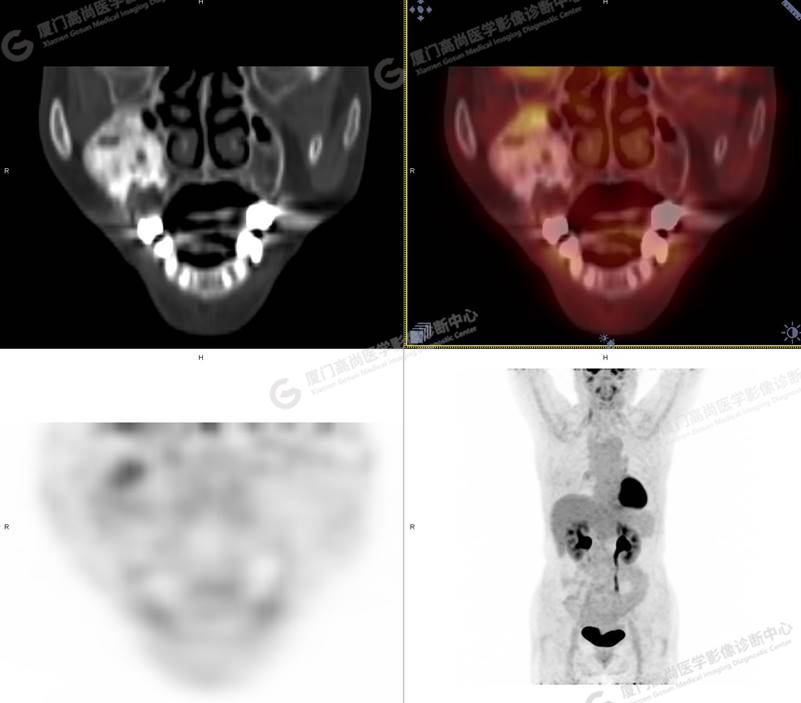

圖1

圖2

圖3

圖4

PET/CT所見:右側(cè)上頜骨、右側(cè)顴骨及右側(cè)額骨骨質(zhì)膨脹,其內(nèi)密度不均勻性增高,部分放射性攝取輕微增高,SUVmax 2.27。